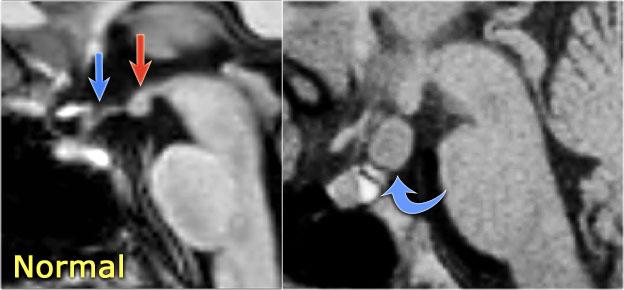

Xơ cứng thùy thái dương trong bên trái. Gliosis kín đáo của hải mã trái (mũi tên xanh dương) và teo não (mũi tên vàng).

Bệnh nhân 35 tuổi với động kinh thùy thái dương kháng trị.

MRI cho thấy tăng tín hiệu kín đáo của hải mã trái trên chuỗi xung FLAIR axial (mũi tên xanh dương) và teo hải mã trái trên hình ảnh coronal (mũi tên vàng).

Bệnh nhân được điều trị thành công bằng phẫu thuật cắt hạnh nhân – hải mã bên trái.

TRÁI: Ngách phễu bình thường của não thất ba (mũi tên xanh), thể vú (mũi tên đỏ). PHẢI: U hamartoma củ xám (tuber cinereum) (mũi tên cong).